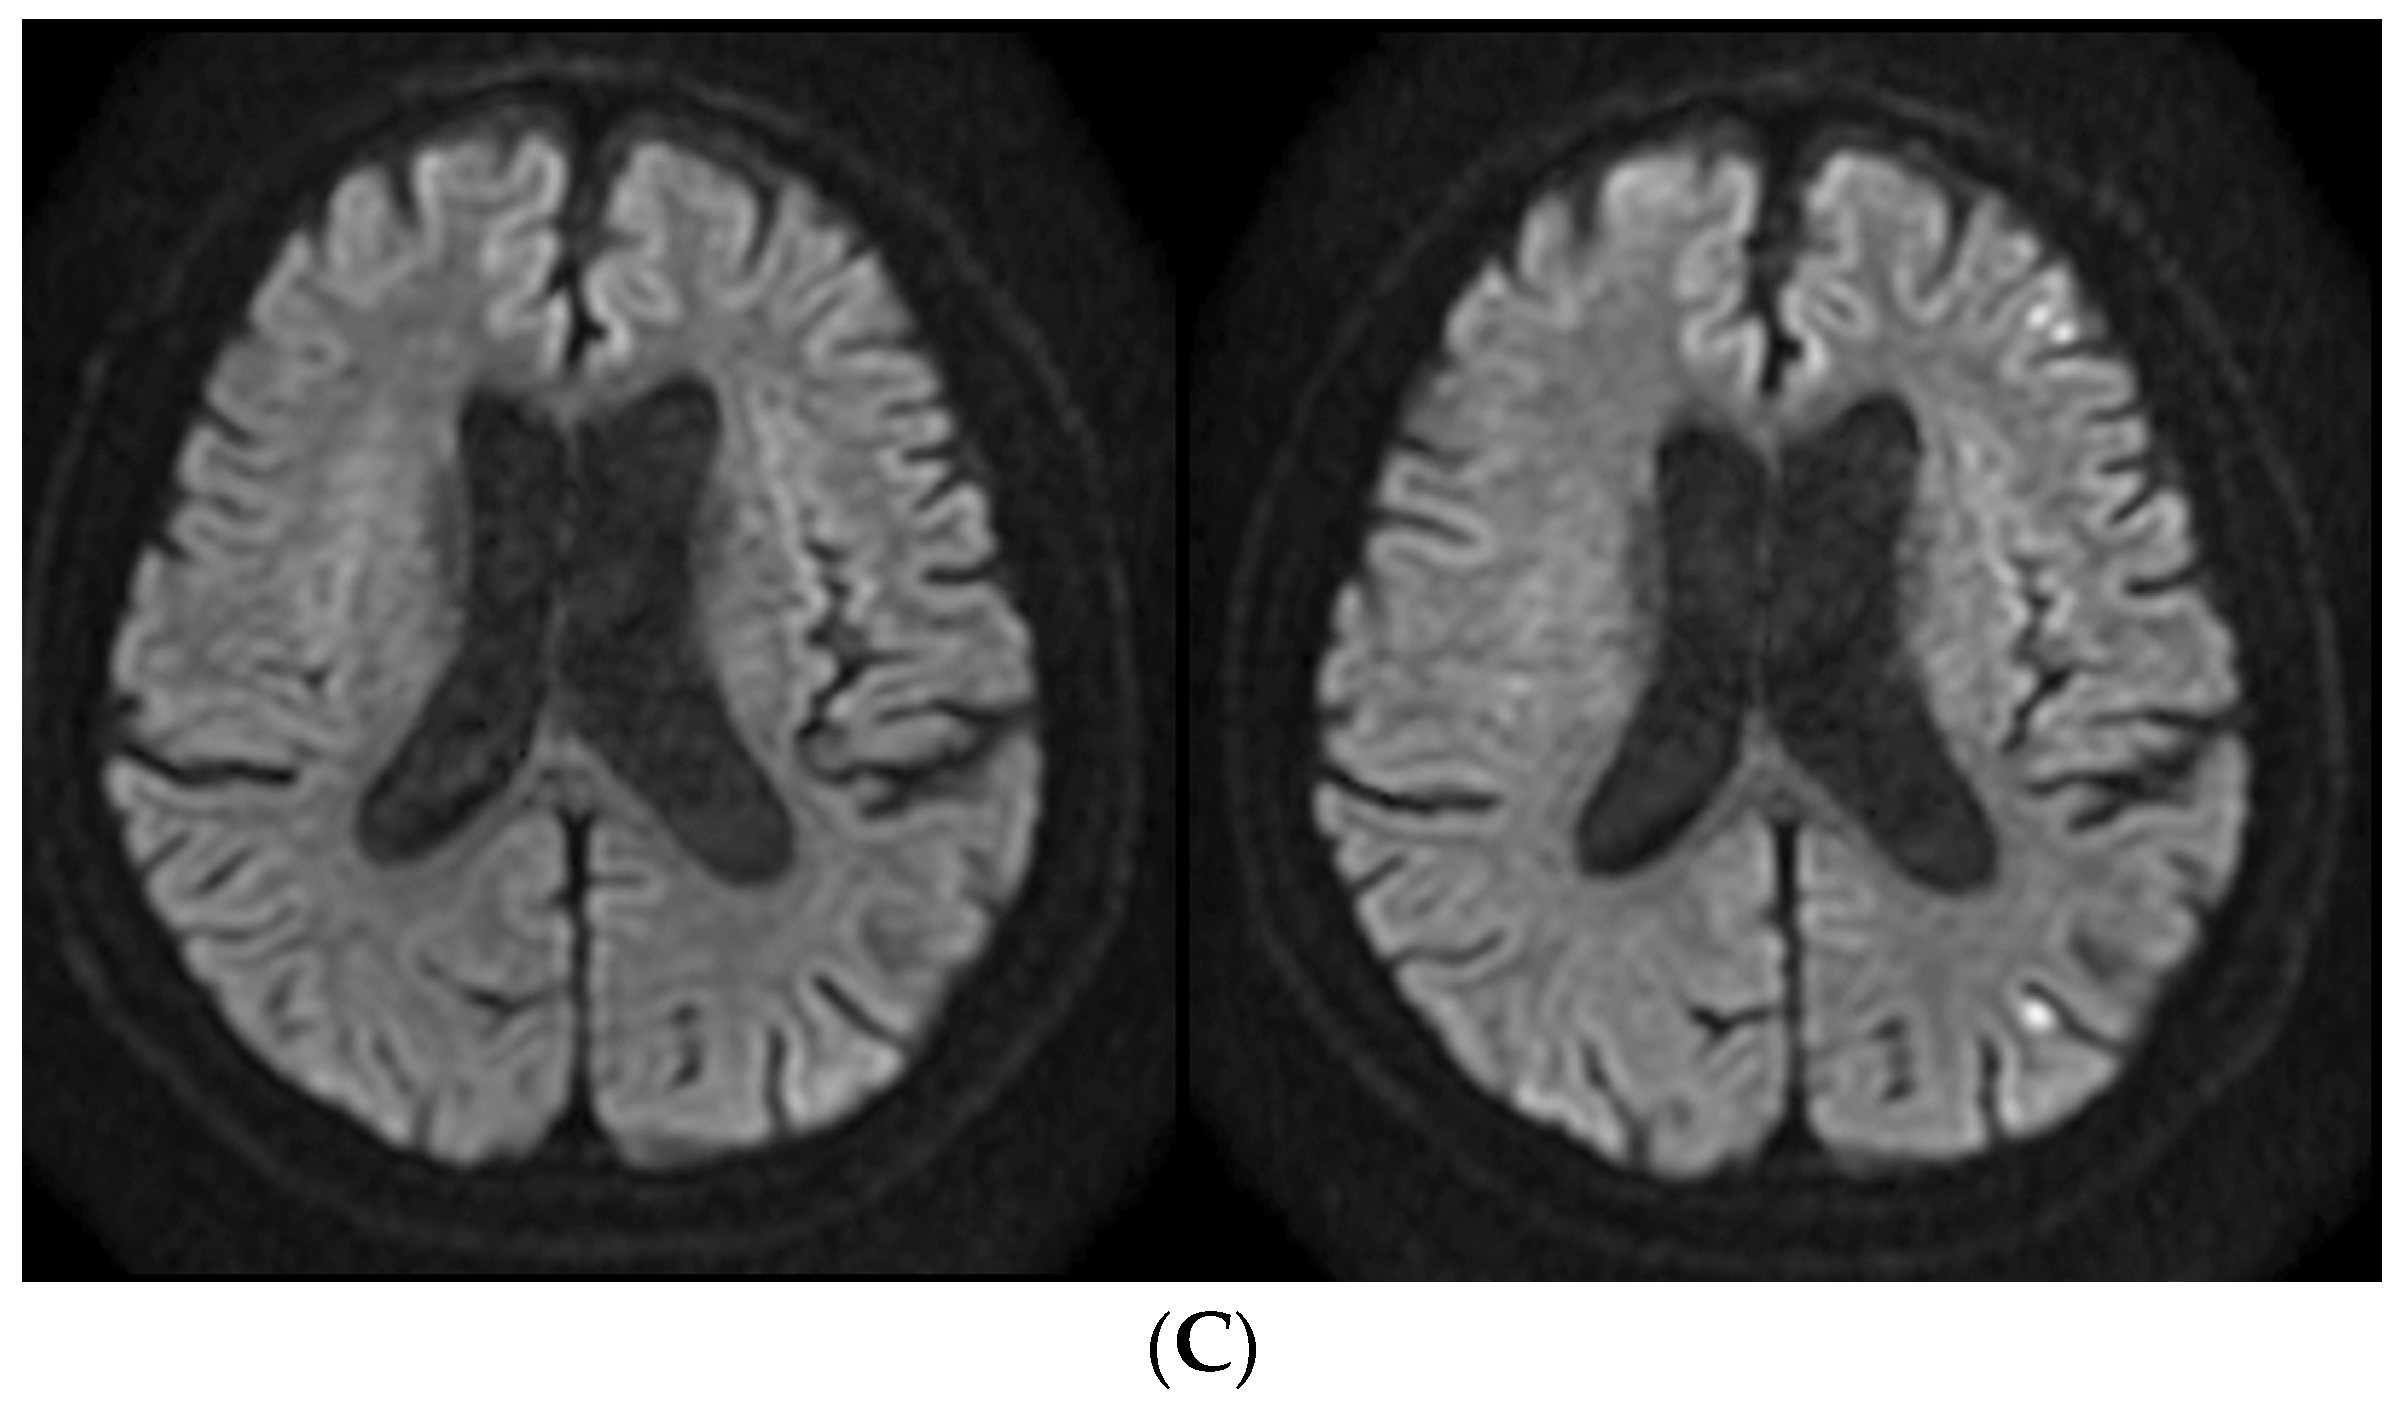

2.5. Case Presentation